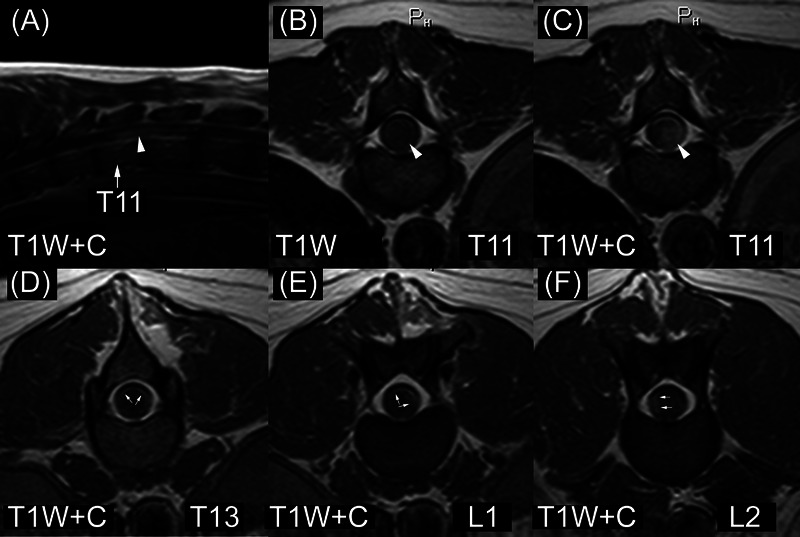

关于犬颅内或脊髓上皮瘤的核磁共振成像外观,公开发表的描述很少。在这项多中心、回顾性、二次分析、病例系列研究中,三位兽医放射科专家独立审查并记录了六只经组织病理学确诊的狗肾上皮瘤(三例颅内病例和三例脊髓病例)的核磁共振成像检查特征。如果对具体特征存在分歧,则达成共识。所有颅内外胚窦瘤都位于前脑,在 T1 加权(T1W)和 T2 加权(T2W)图像中信号强度不均匀,对比度增强不均匀,T2W 图像中信号强度过高。两例脑外膜瘤位于脑室内,一例位于轴内。其他成像特征包括内部囊肿样结构、内部出血和周围水肿。患脊髓外胚瘤的狗的髓内病变位于颈部或胸部脊髓。脊髓外皮瘤在 T1W 图像中呈等密度和均匀性,在 T2W 图像中呈高密度。病变相对于脊髓中央管的位置各不相同。所有三个脊髓外胚瘤体周围都有 T2W 高密度和中度异质对比度增强。没有一个脊髓外胚瘤内生囊肿样结构。其中一个脊髓外胚瘤体有下坠转移(弥漫性、脑外膜)的迹象。犬肾上皮瘤的磁共振成像特征与其他脑部和脊髓疾病的特征重叠。对于患有脑室内、前脑轴内或脊髓髓内肿块的犬,应将附脑瘤作为鉴别诊断的一个因素。

There are few published descriptions of the MRI appearance of canine intracranial or spinal cord ependymoma. In this multicenter, retrospective, secondary analysis, case series study, three veterinary radiologists independently reviewed and recorded imaging characteristics of MRI studies in six dogs with histopathologically confirmed ependymoma (three intracranial and three spinal cord cases). A consensus was reached when there was disagreement on specific features. All intracranial ependymomas had forebrain location, heterogeneous signal intensity in T1-weighted (T1W) and T2-weighted (T2W) images, heterogeneous contrast enhancement, and hyperintensity in T2W images. Two ependymomas had an intraventricular location; one was intra-axial. Other imaging features included intralesional cyst-like structures, intralesional hemorrhage, and perilesional edema. Dogs with spinal cord ependymoma had intramedullary lesions located in the cervical or thoracic spinal cord. Spinal cord ependymomas were isointense and homogeneous in T1W images and hyperintense in T2W images. Lesion location relative to the central canal of the spinal cord was variable. All three spinal cord ependymomas had perilesional T2W hyperintensity and moderate, heterogeneous contrast enhancement. None of the spinal cord ependymomas had intralesional cyst-like structures. One spinal cord ependymoma had evidence of drop metastases (diffuse, leptomeningeal). MRI features of canine ependymomas overlap with those of other diseases of the brain and spinal cord. Ependymoma should be considered a differential diagnosis for dogs with intraventricular, intra-axial forebrain, or intramedullary spinal cord masses.